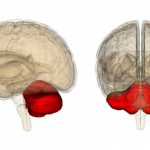

Mokslininkai sukūrė sintetines smegenėles, kurios gali pakeisti pažeistas žmogaus smegenų dalis, arba tas dalis, kurios veikia netinkamai.

Sukurtosios dirbtinės smegenėlės daugiau ar mažiau yra paprasta mikroschema, tačiau ji gali gauti elektrinius impulsus iš smegenų kamieno, suprasti nervinius signalus ir siųsti skirtingus singalus atgal į konkrečius smegenų kamieno regionus.

Kolkas tokiu būdu galima valdyti tik pagrindinius judėsius, tačiau mokslininkai teigia, kad šis pasiekimas yra svarbus žingsnis pirmyn kuriant dirbtines smegenis.

Bandymas buvo atliktas su žiurkėmis. Mokslininkai išjungė jų smegenis ir prijungė mikroschemą elektrodais. Prieš tai buvo atliktas bandymas, kaip žiurkė mirksi reaguodama į dirgiklius. Prijungus mikroschemą, gyvūnas greitai sugebėjo atkartoti tokį patį judėsį.

Nors tai yra tik mažas judėsiukas, tai suteikia daug žinių, kaip galima manipuliuoti smegenų veikla. Sistema dar turės būti gerokai sumažinta, kad galėtų būti naudojama žmogaus kūne. Kolkas jos naudojimo pradžia numatoma tik tolimoje ateityje.

Tokia sistema galėtų pakeisti sukrėtimo metu pažeistas smegenų dalis, nervų sistemą arba senatvėje sunykusias smegenų dalis.